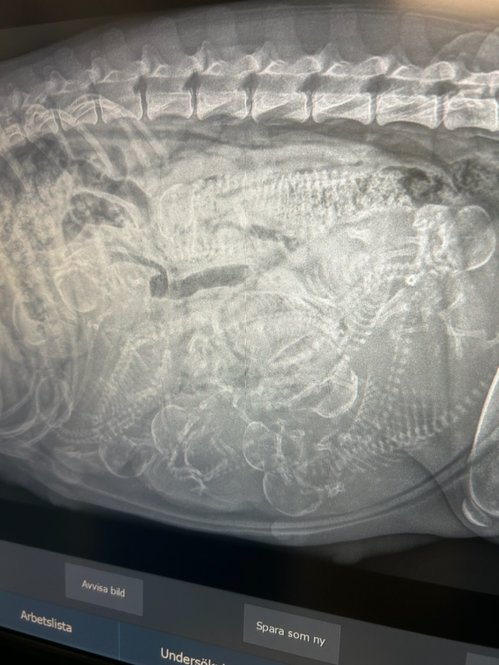

2025.06.30

Idag var vi och röntgade Lura och kan konstatera att det ligger valpar i magen

Lura är pigg och glad, och riktigt rund